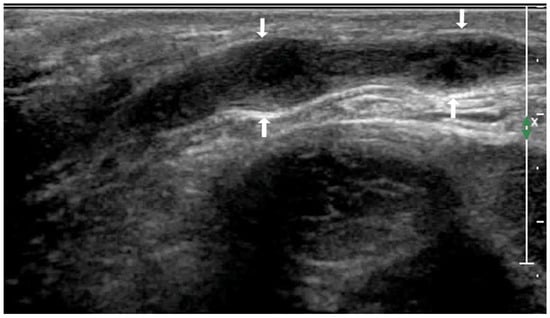

| Lesions conglomeration | + | 10/17 (58.82%) | 6/28 (21.42%) | 6.455 | 0.023 |

| − | 7/17 (41.17%) | 22/28 (78.57%) | |||

| Sinus canal, skin rupture | + | 0 | 2/28 (7.14%) | NA | 0.519 |

| − | 17/17 (100%) | 26/28 (92.85%) | |||